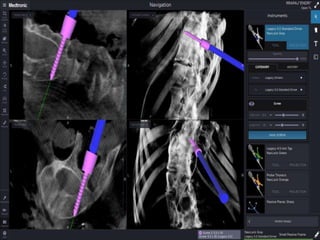

Προεγχειρητική

εκτίμηση και

σχεδιασμός

Stable vertebra

Δυναμικές x-rays

CT Scan

MR-I

Neuro-monitoring

Navigation system